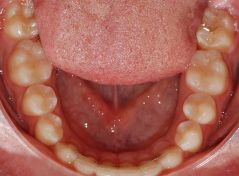

Paziente di 11 anni, Diastemi multipli, corretto con ortodonzia fissa in 20 mesi

correzione di diastemi multipli in 20 mesi

inizio trattamento